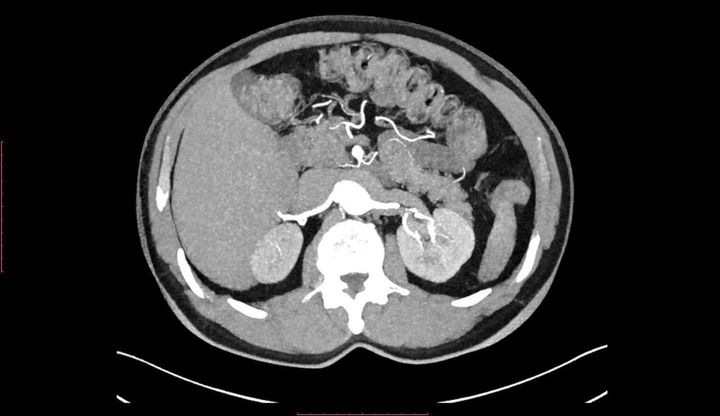

胸郭と腹部のCTスキャン画像

※写真はイメージです